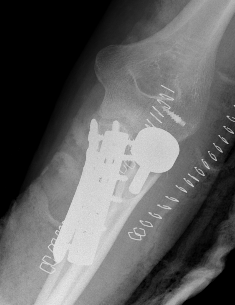

Olecranon plate + ORIF Type II coronoid process + radial head replacement

Olecranon plate with radial head replacement

Olecranon plate with radial head replacement + LCL repair

Olecranon plate + medial coronoid buttress plate + radial head replacement

Complex proximal ulna fracture with radial head replacement subluxation